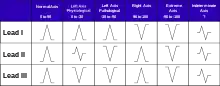

Ventricles contain more muscle mass than the atria. Therefore, the QRS complex is considerably larger than the P wave. The QRS complex is often used to determine the axis of the electrocardiogram, although it is also possible to determine a separate P wave axis.

Looking at the precordial leads, the R wave usually progresses from showing an rS-type complex in V1 with an increasing R and a decreasing S wave when moving toward the left side. There is usually a qR-type of complex in V5 and V6, with the R-wave amplitude usually taller in V5 than in V6. It is normal to have a narrow QS and rSr' patterns in V1, and this is also the case for qRs and R patterns in V5 and V6. The transition zone is where the QRS complex changes from predominantly negative to predominantly positive (R/S ratio becoming >1), and this usually occurs at V3 or V4. It is normal to have the transition zone at V2 (called "early transition") and at V5 (called "delayed transition").[11] In biomedical engineering, the maximum amplitude in the R wave is usually called "R peak amplitude", or just "R peak".[12][13] Accurate R peak detection is essential in signal processing equipment for heart rate measurement and it is the main feature used for arrhythmia detection.[14][15]

The definition of poor R wave progression (PRWP) varies in the literature. It may be defined, for example, as R wave of less than 2–4 mm in leads V3 or V4 and/or presence of a reversed R wave progression, which is defined as R in V4 < R in V3 or R in V3 < R in V2 or R in V2 < R in V1, or any combination of these.[11] Poor R wave progression is commonly attributed to anterior myocardial infarction, but it may also be caused by left bundle branch block, Wolff–Parkinson–White syndrome, right and left ventricular hypertrophy, or a faulty ECG recording technique.[11]